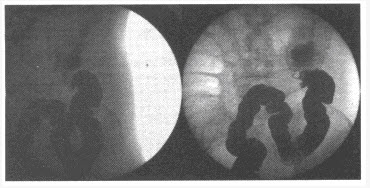

女,45岁,大便习惯改变半年余,粪便变细,黏液血便1个月。结合图像,最可能的诊断为()

A:肠扭转

B:肠套叠

C:降结肠癌

D:肠穿孔

E:降结肠炎